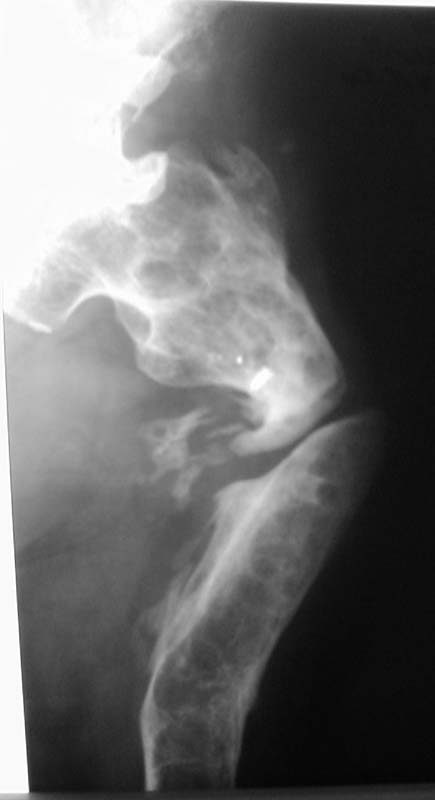

Просится "русский замок" с последующим удлинением на двух уровнях. Нельзя ли посмотреть тазобедренный сустав?